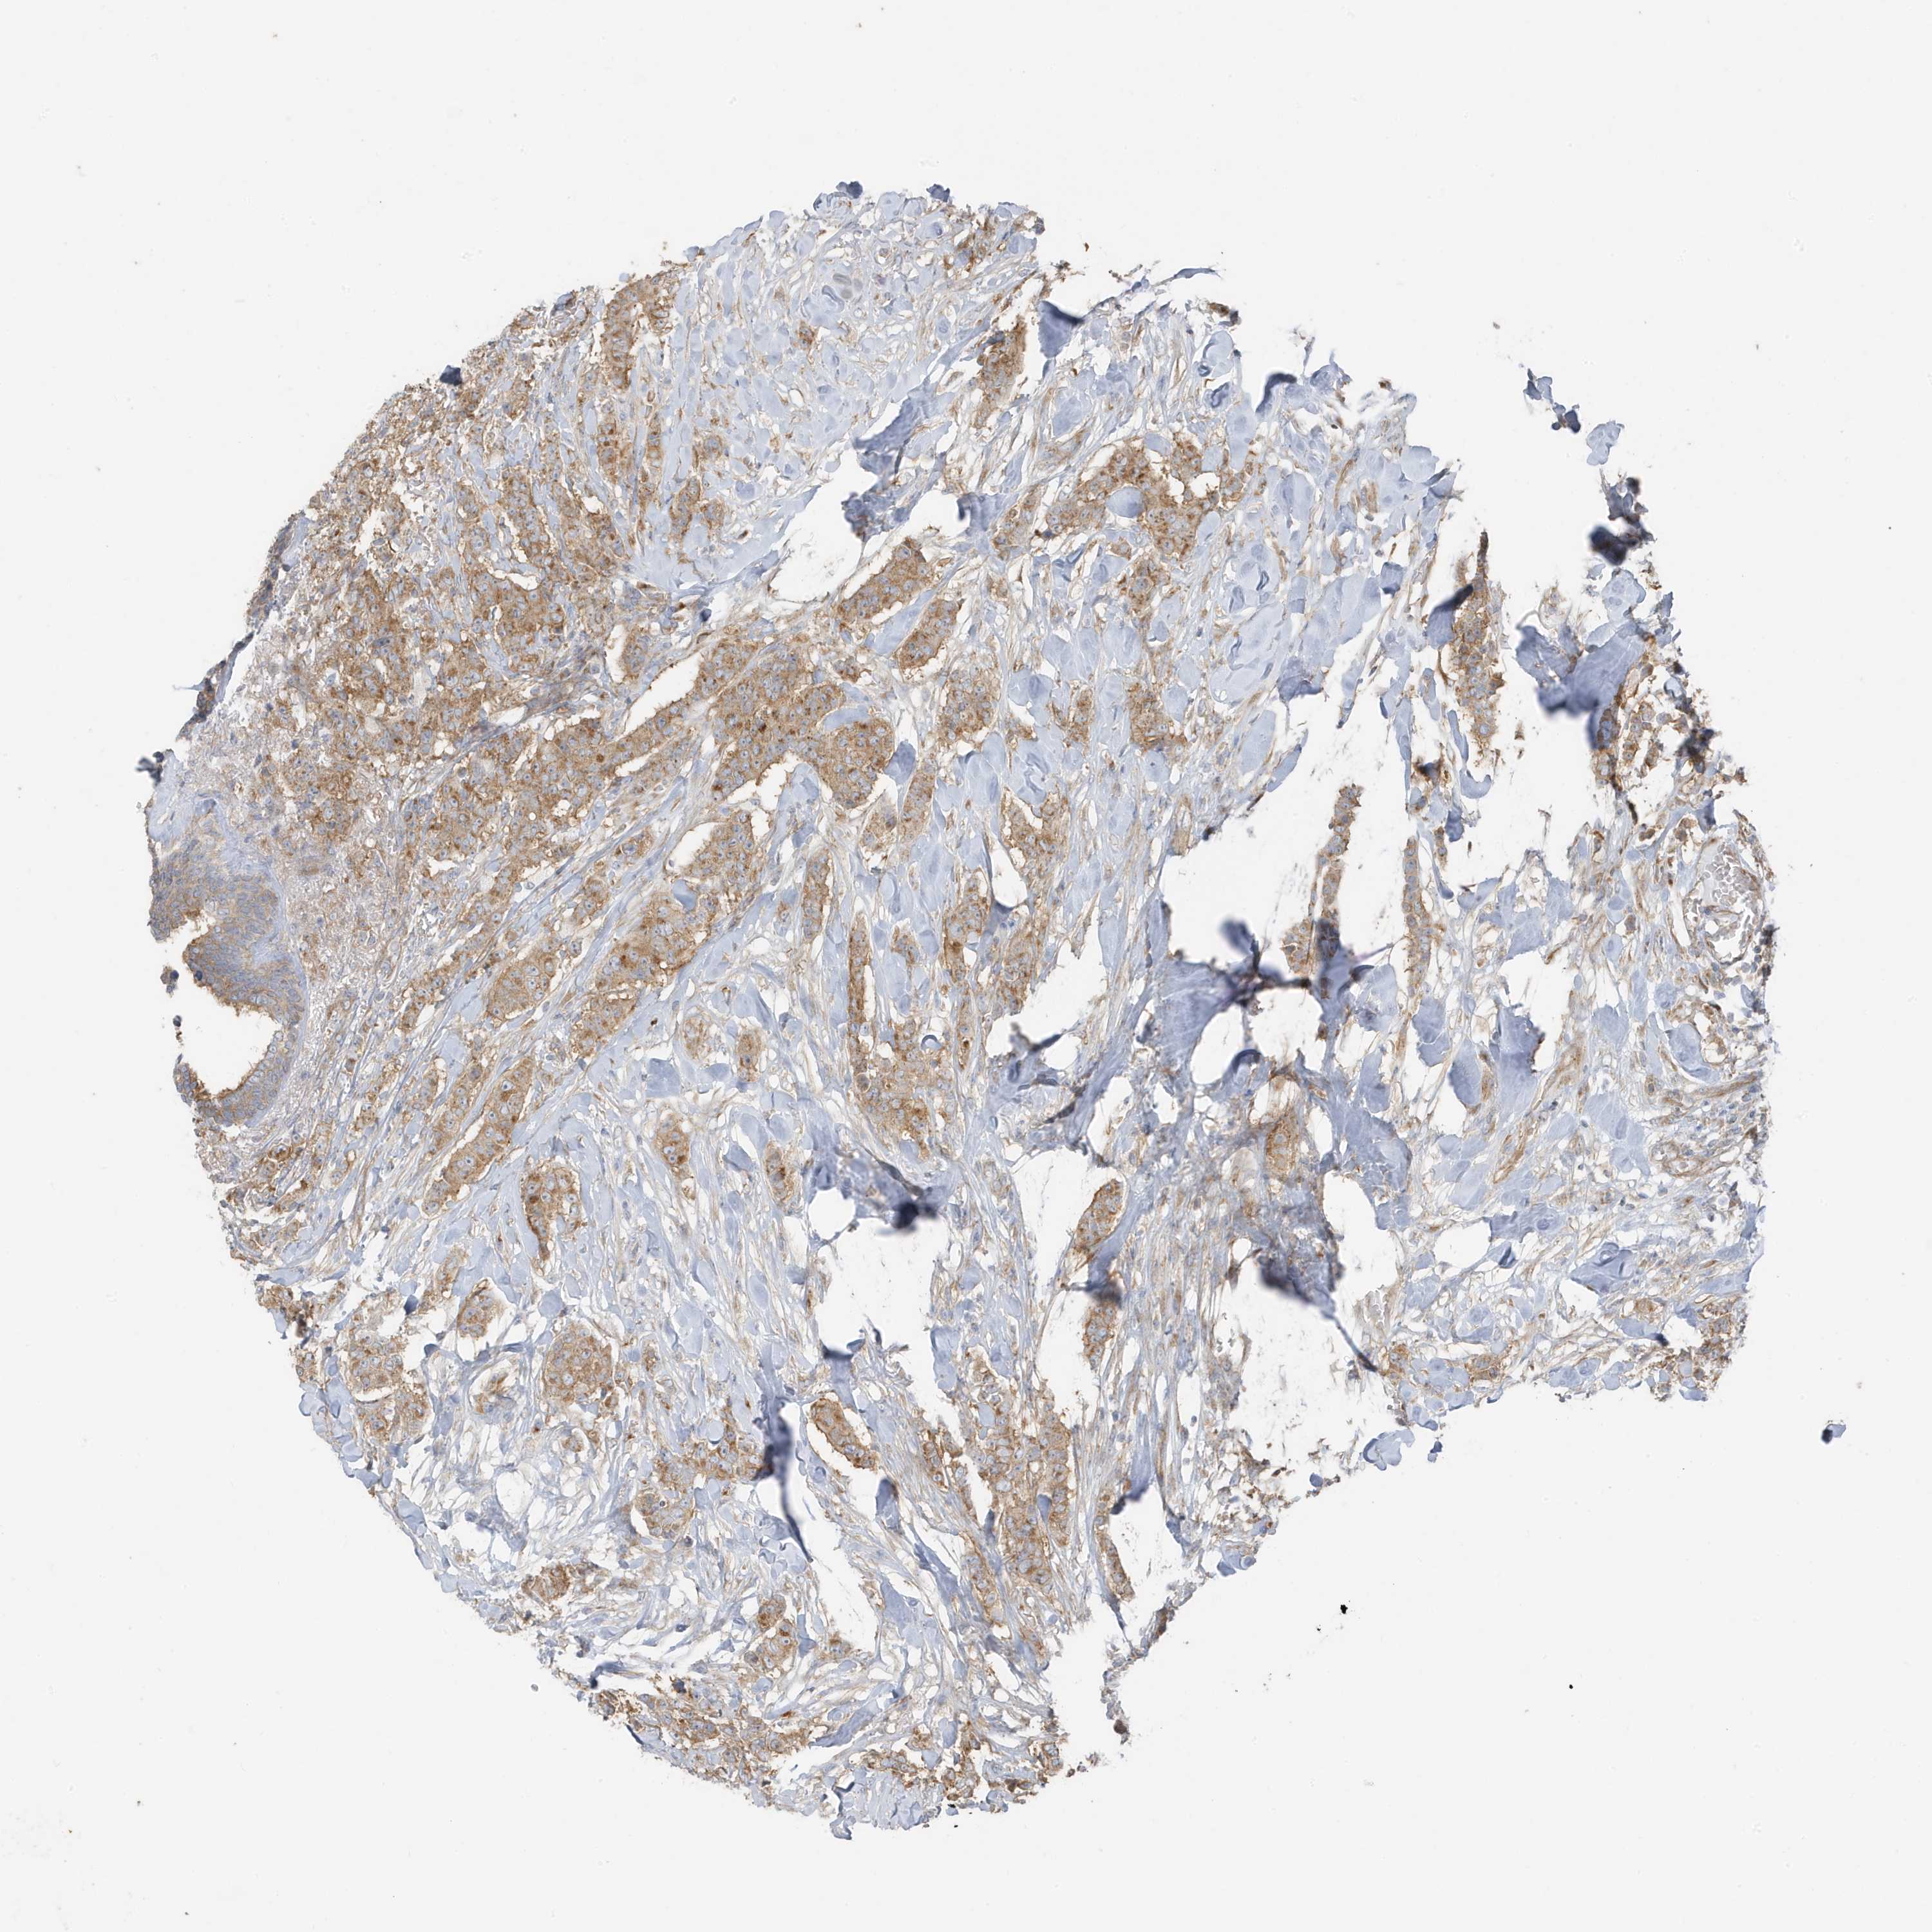

CANCER BREAST CANCER Show tissue menu

BRCA TCGA BRCA VALIDATION PROTEIN EXPRESSION